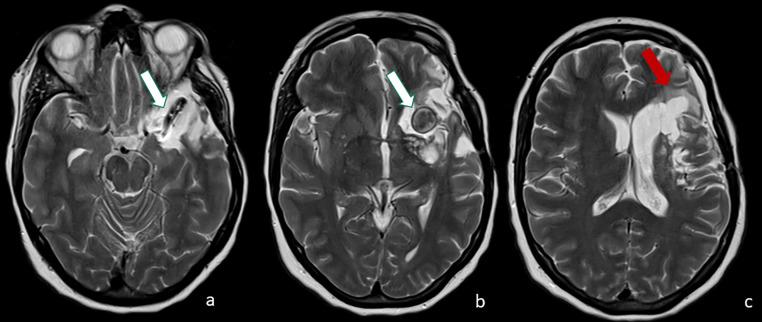

Giant serpentine aneurysms are rare huge and partially thrombosed aneurysms, with an eccentric tortuous intra-aneurysmal vascular channel. Surgical treatment is often necessary due to the great mass effect. We describe a case of a left-handed woman with a giant serpentine aneurysm of the left middle cerebral artery whose management was complex. The challenge was to exclude the aneurysm from circulation, reduce the mass effect, and, mostly, preserve the language function. Since the patient was left-handed the language dominance needed to be assessed; functional MRI (fMRI) and Wada test (WT) showed a right dominance. Surgical treatment was performed, as a complication, the patient developed left fronto-basal ischemia with a slight paresis of the right hand but without any language deficit. Our case shows the importance of a multidisciplinary team in patient management, with a pivotal role of neuroradiological functional tests in presurgical planning.

巨大蜿蜒状动脉瘤是罕见的巨大且部分血栓形成的动脉瘤,具有偏心迂曲的瘤内血管通道。由于巨大的占位效应,通常需要进行手术治疗。我们描述了一例左手中风的女性患者,患有左大脑中动脉巨大蜿蜒状动脉瘤,其治疗过程复杂。面临的挑战是将动脉瘤排除在循环之外,减轻占位效应,并且最重要的是保留语言功能。由于患者是左利手,需要评估语言优势半球;功能磁共振成像(fMRI)和Wada试验(WT)显示为右侧优势半球。进行了手术治疗,作为并发症,患者出现左额底部缺血,右手轻度无力,但无任何语言缺陷。我们的病例显示了多学科团队在患者管理中的重要性,神经放射学功能测试在术前规划中起着关键作用。